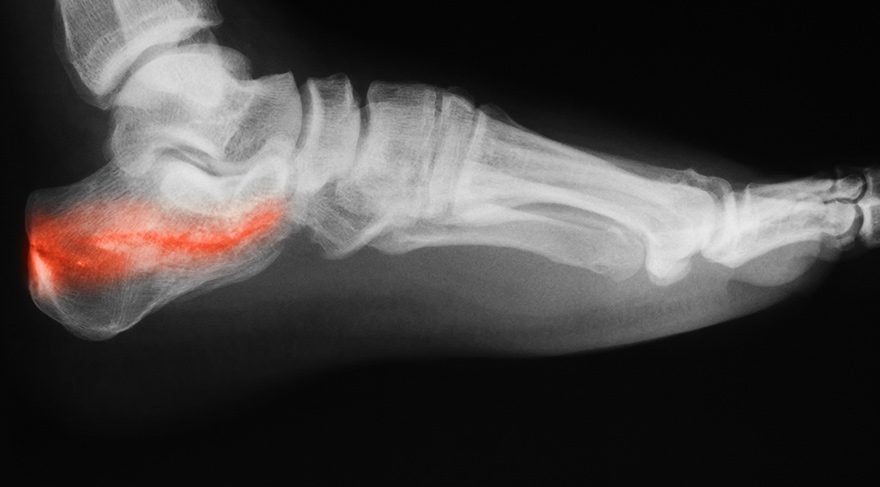

Erişkinlerde topuk ağrısının en sık sebebidir. Aslında ağrıya sebep olan ayak röntgeninde kalkaneus kemiğinde gözüken çıkıntı (epin kalkanei) değildir. Yapılan birçok araştırmada özellikle 50 yaş üstü erişkinlerde başka bir sebeple çekilen ayak röntgenlerinde bu çıkıntının gözüktüğü ve hastaların en az yarısında topuk ağrısından yakınmadıklarını göstermiştir. Ortopedistler olarak hastalarımızı tedavi ederken bu çıkıntıyı ortadan kaldırmak gibi bir amacımız hiç bir zaman olmaz.

Vücudumuzun ağırlığını yere ileten plantar fasia denilen bir zardır. Bu yapı topuk kemiği ile ayak parmaklarımızın tabanına yapışır. Ağrıya sebep olan ise bu yapının bazı sebeplerden dolayı esnekiliğini kaybedip topuk kemiğine yapıştığı yerde oluşturduğu yangıdır(plantar fassit). Oluşan kemik çıkıntısı ise bu yangının sonuçlarından biridir.